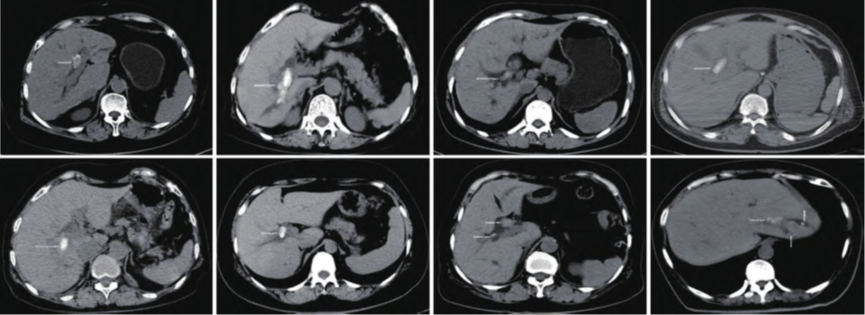

8例肝胆管结石患者液电碎石治疗的CT表现(白色箭头所指为结石)